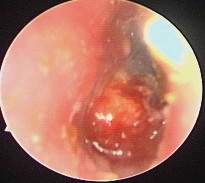

Ảnh 17 Nụ hạt trên màng nhĩ MSBA. 1811254229 |

Ảnh 18 Còn lỗ thủng MSBA. 1904282172 |